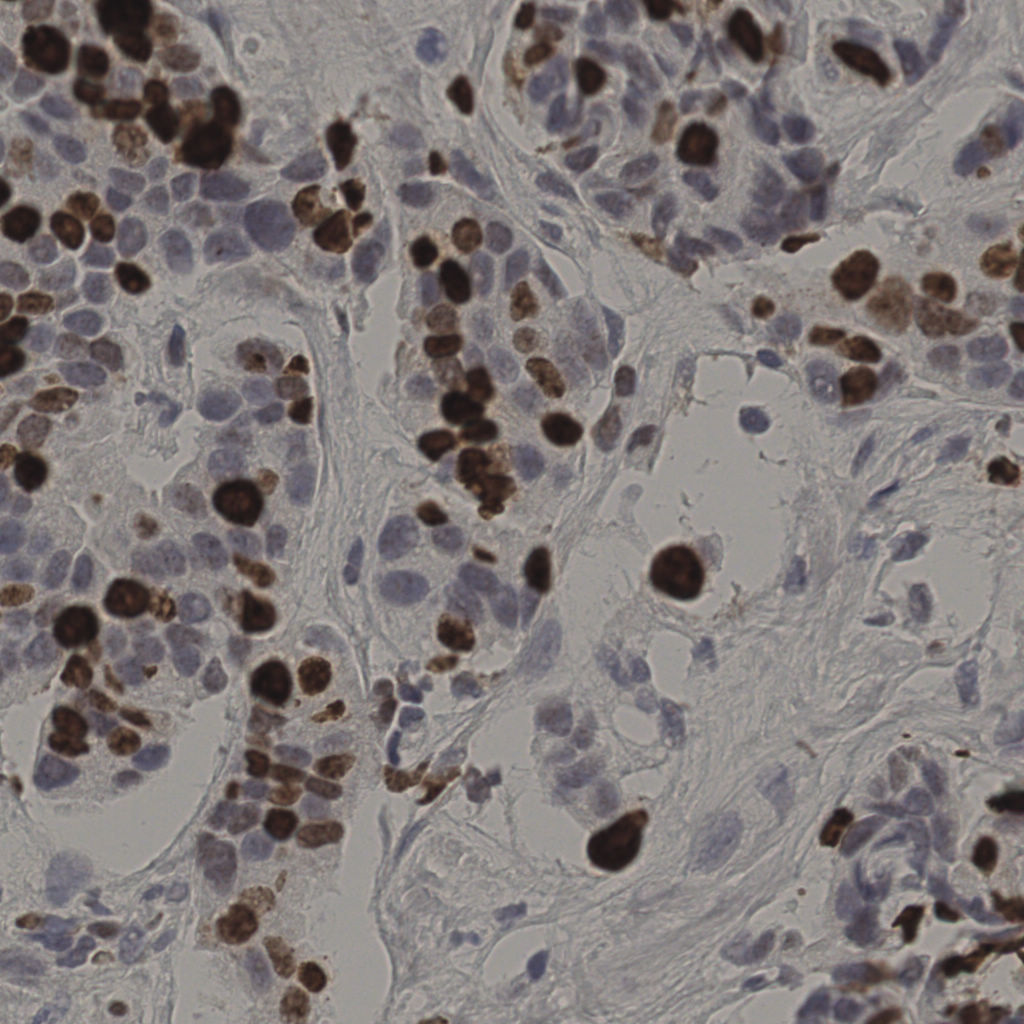

17.75%

Ki67 指数

阴 7986

阳 1723